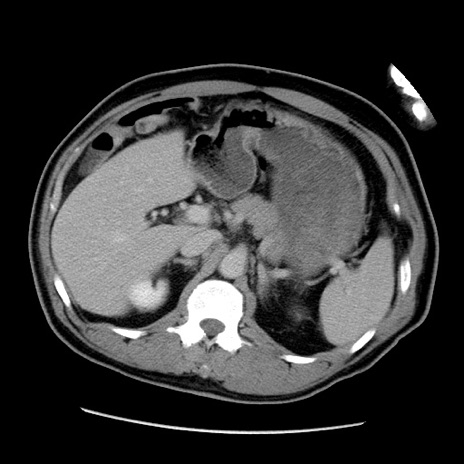

症例22(横断像)

【症例】50歳代男性

【主訴】腹痛

【現病歴】AVMからの被殻出血のため回復期リハ病棟入院中。 本日午後3時頃急に下腹部痛が出現した。

【既往歴】AVM、被殻出血、虫垂炎、高血圧

【身体所見】意識晴明、左半身不全麻痺、会話の理解は良好、36.5°C、腹部:膨隆、全体に板状硬、下腹部正中に圧痛点あり、反跳痛-、筋性防御不明、右下腹部にope scar

【データ】WBC 9400、CRP 0.06